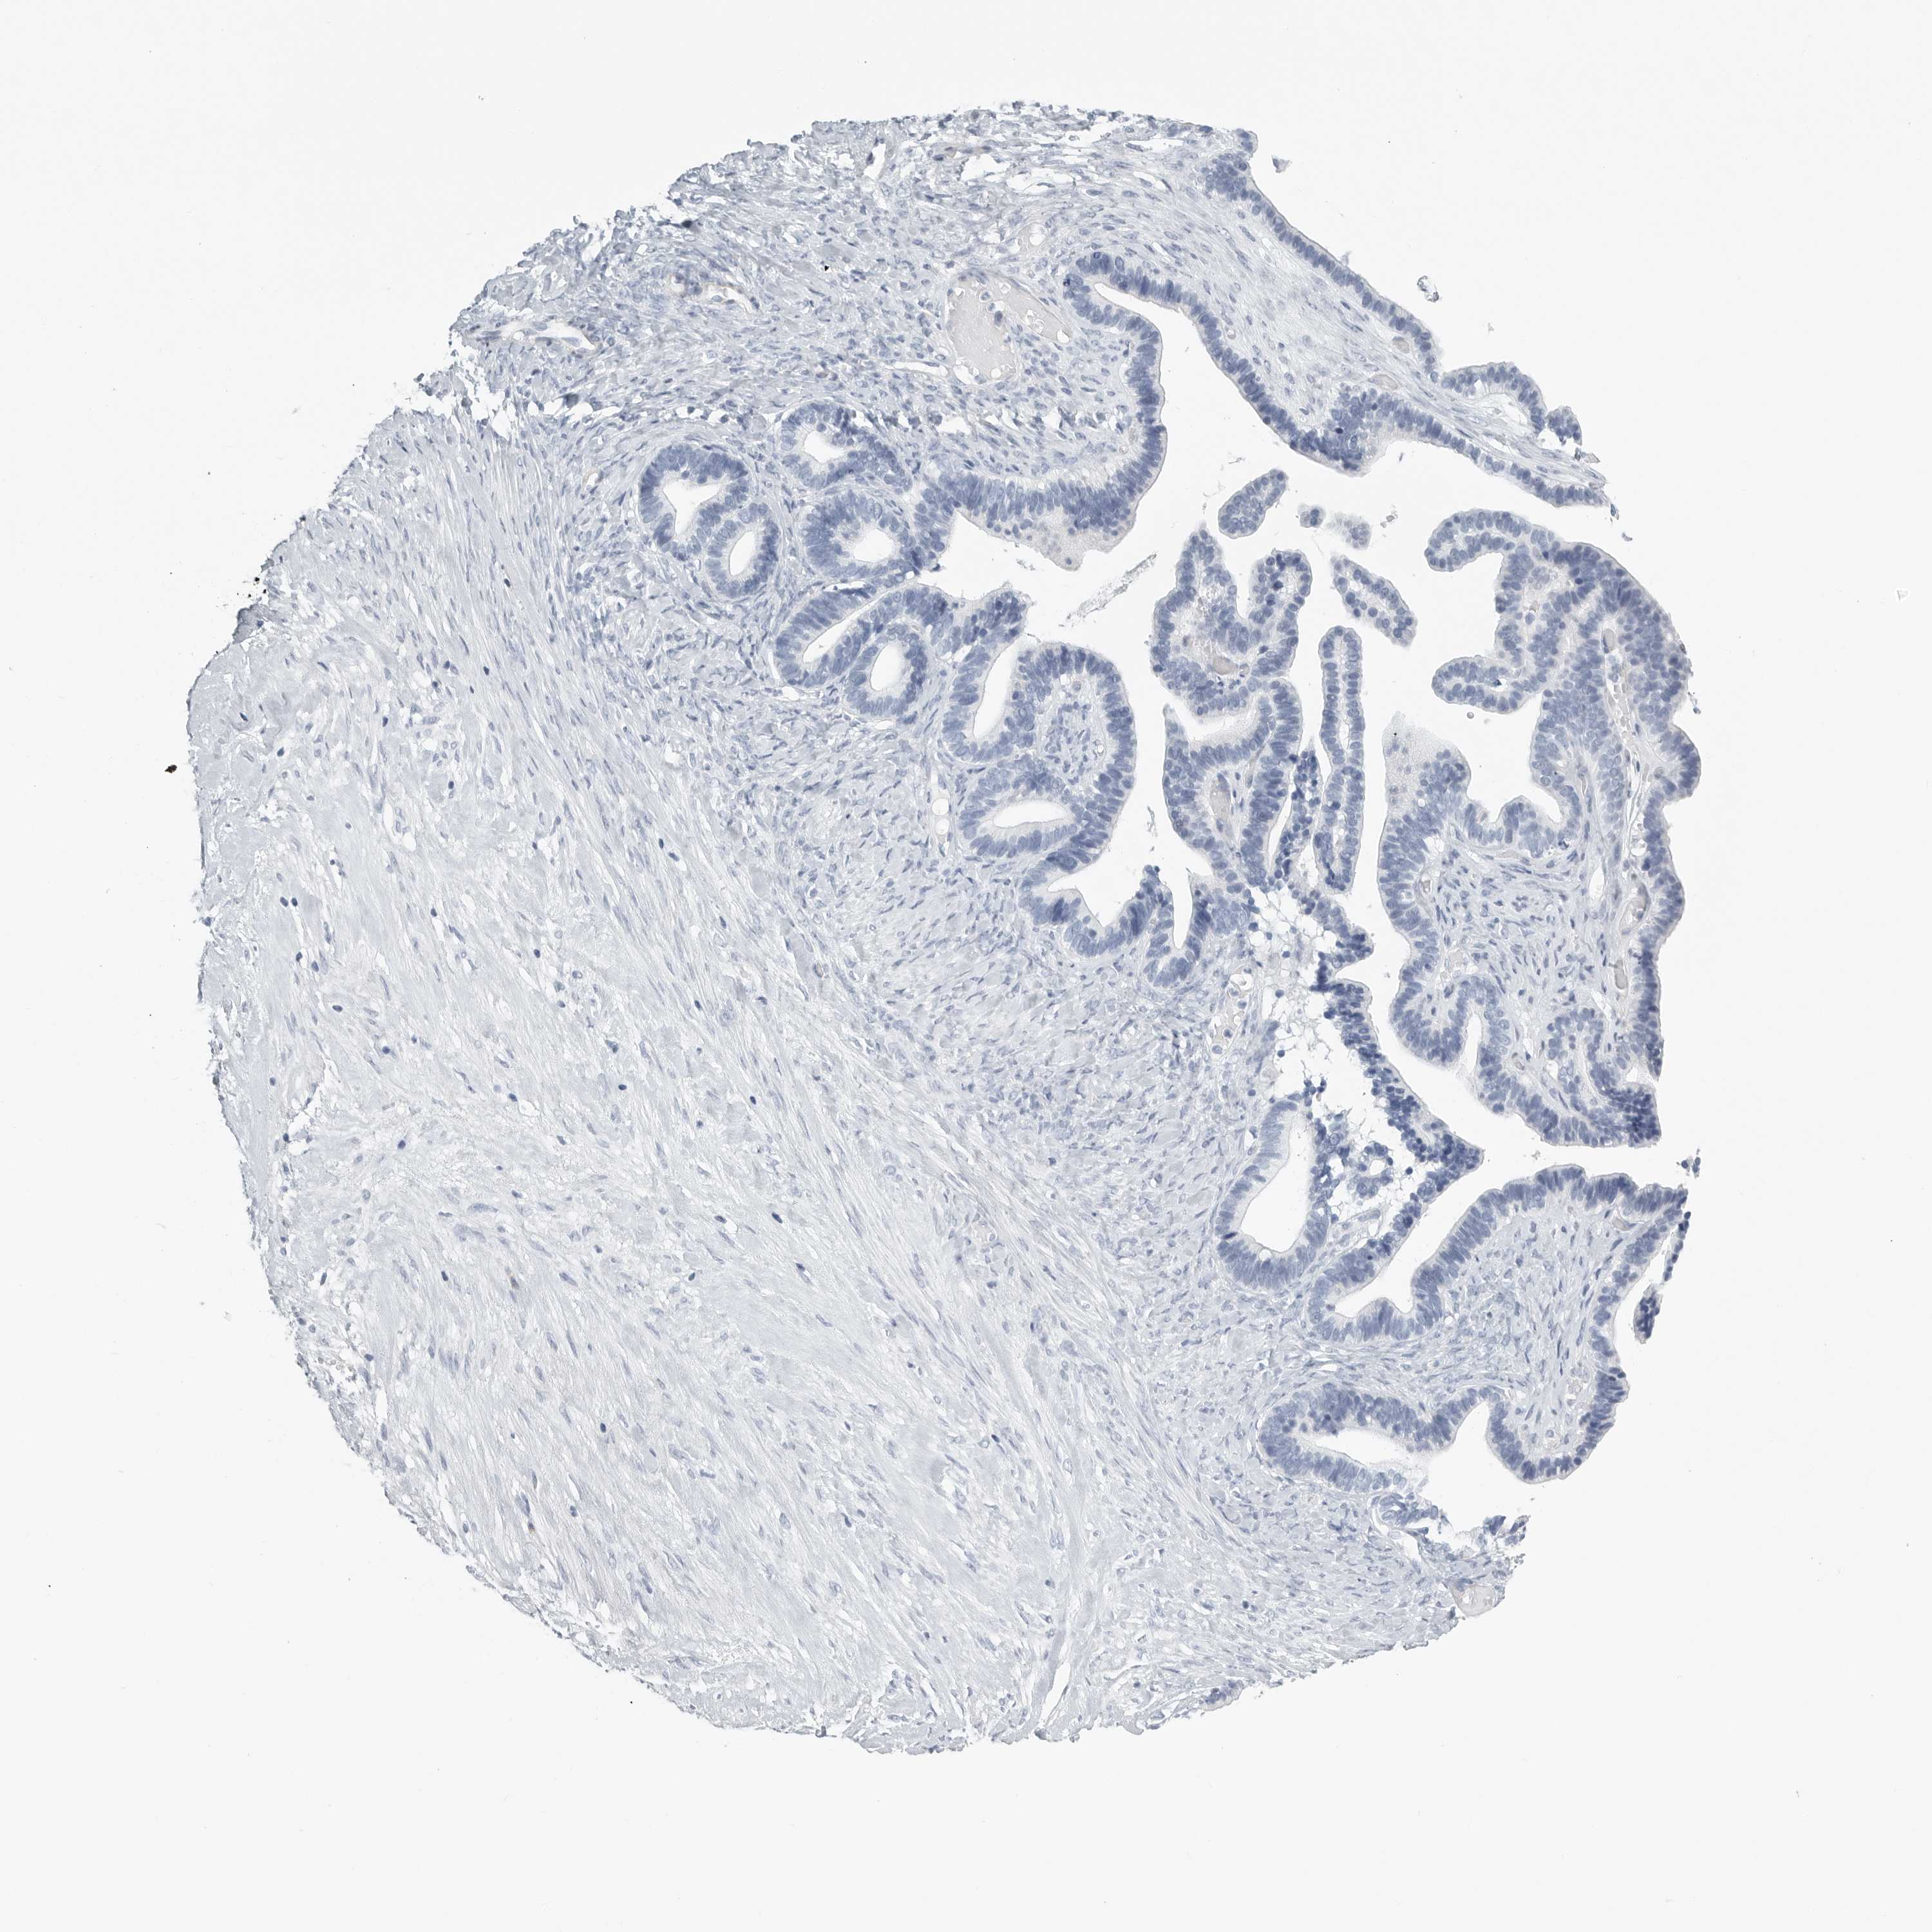

OVARIAN CANCER - Protein expressioni

A mouse-over function shows sample information and annotation data. Click on an image to view it in a full screen mode. Samples can be filtered based on level of antibody staining by selecting one or several of the following categories: high, medium, low and not detected. The assay and annotation is described here.

Note that samples used for immunohistochemistry by the Human Protein Atlas do not correspond to samples in the TCGA dataset.

Antibody stainingi

Antibody staining in the annotated cell types in the current human tissue is reported as not detected, low, medium, or high, based on conventional immunohistochemistry profiling in selected tissues. This score is based on the combination of the staining intensity and fraction of stained cells.

Each image is clickable and will lead to virtual microscopy that enables deeper exploration of all samples and also displays staining intensity scores, fraction scores and subcellular localization as well as patient and tissue information for each sample.

Antibody HPA027134

Antibody HPA027150

Antibody HPA029859

Antibody CAB022343

Staining

High

Medium

Low

Not detected

Intensity

Strong

Moderate

Weak

Negative

Quantity

>75%

75%-25%

<25%

None

Location

Nuclear

Cytoplasmic/membranous

Cytoplasmic/membranous,nuclear

Cystadenocarcinoma, serous, NOS

Carcinoma, endometroid

Cystadenocarcinoma, mucinous, NOS

Carcinoma, NOS